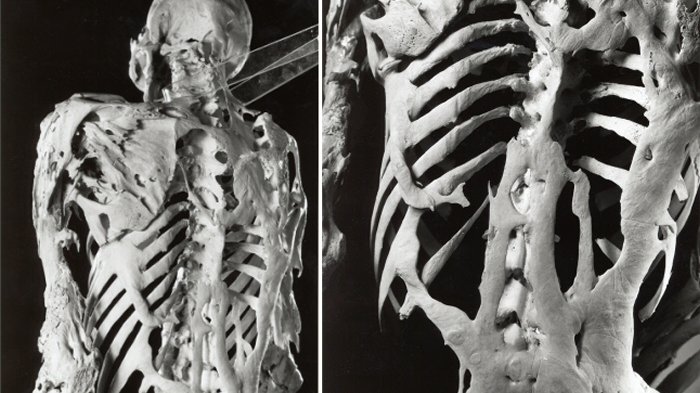

Stone Man’s disease digambarkan sebagai mutasi dari mekanisme perbaikan tubuh di mana muncul pertumbuhan tulang baru

Stone Man’s disease digambarkan sebagai mutasi dari mekanisme perbaikan tubuh di mana akan muncul pertumbuhan tulang baru di tempat otot, tendon, ligamen, dan jaringan ikat lainnya yang cedera seharusnya berada.

Tulang-tulang ini berkembang di seluruh sendi sehingga membatasi gerakan dan membentuk kerangka kedua, mengubah mereka menjadi patung hidup.